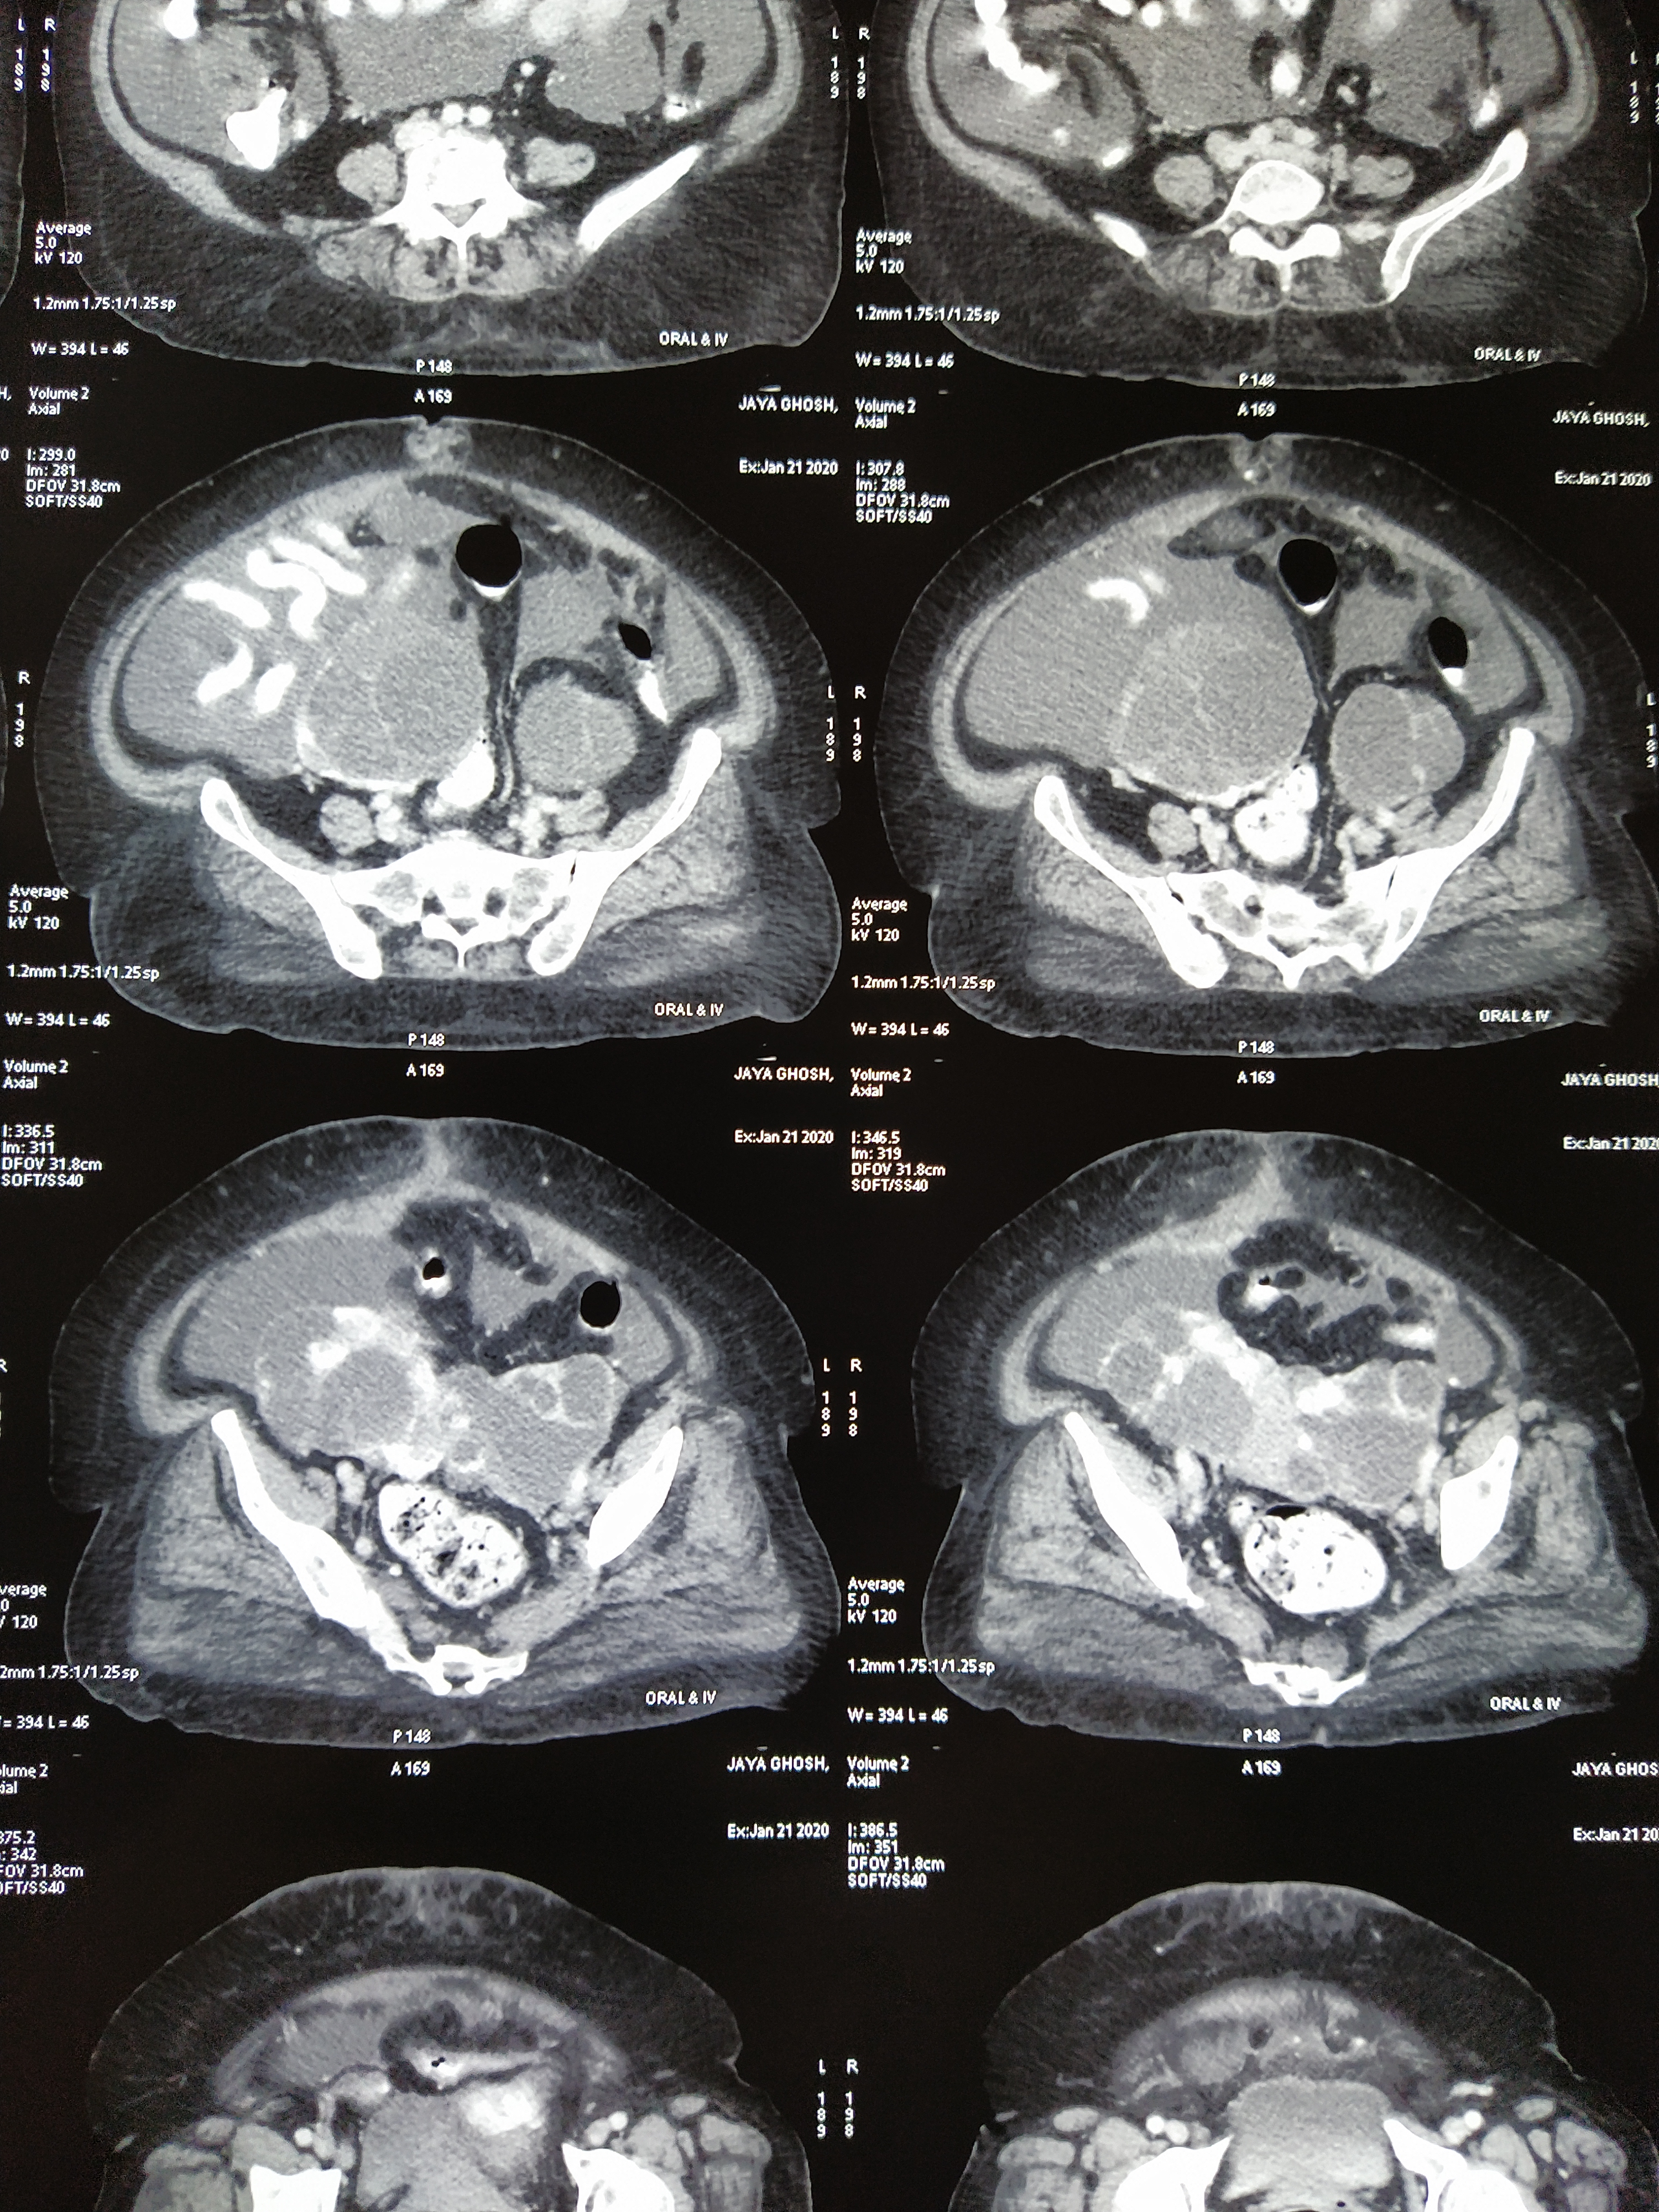

Abdominal CT scan, plain and with contrast shows ovarian mass (10.9x8.7cm2 on right ovary; 8.7x7.0 cm2 on left ovary) with multiple enlarged lymph nodes. CECT whole abdomen was advised and also reported that there is abdominal wall hernia at umbilicus with hernia orifice of 2 cm and bilateral ovarian tumour (Figure 1).

Figure 1 CT scan of SMJN mimics umbilical hernia.